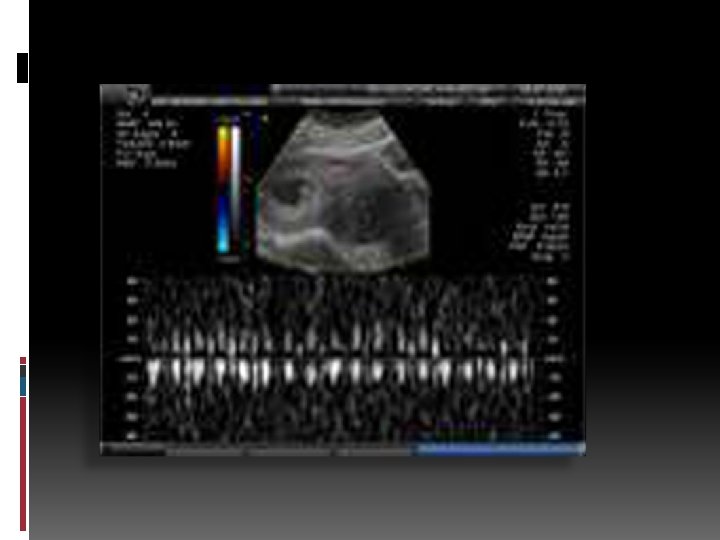

Diagnóstico ØAnamnesis (Historia clínica) Ø Examen físico. Ø Imagenología.